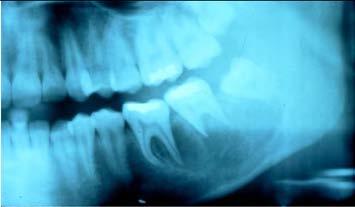

What is this radiographic finding?

Aneurysmal Bone Cyst

✎ There’s a radiolucency involving the second molar

that’s going as far anterior as the first molar and back

to the third molar

✎ There is a little bit of spiking root resorption and

that’s one of the signs that we associate with

malignancy

✎ It’s a little bit ill-defined ~ hard to say exactly

where it begins and ends